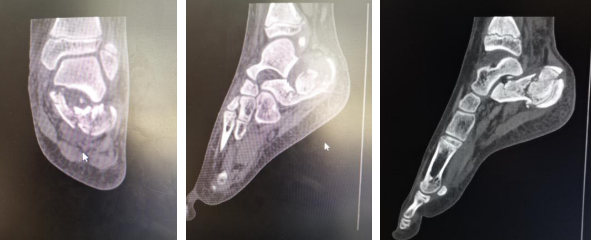

很快,曹广超主任手术团队为小患者进行了左跟骨骨折关节镜下撬拨复位内固定术,关节镜进入距下关节腔内,一次性刨削器清理充血关节内滑膜组织,清理软骨缺损处,见跟骨粉碎骨折,关节面塌陷,关节镜监视下复位,克氏针撬拨复位塌陷的关节面骨块,多枚克氏针临时固定,手法推挤,恢复跟骨宽处及长度,C型臂透视及关节镜检查骨折复位满意后,拧入4枚空心螺钉固定。顺利结束手术。

术中,克氏针撬拨复位满意,多枚空心螺钉固定